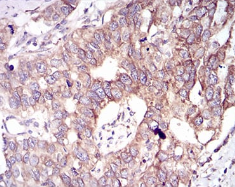

GSK3B Mouse Monoclonal antibody[3D6B4]

AC2395 GSK3B Mouse Monoclonal antibody[3D6B4] 100ug $367 10days

IHC    1/200 - 1/1000